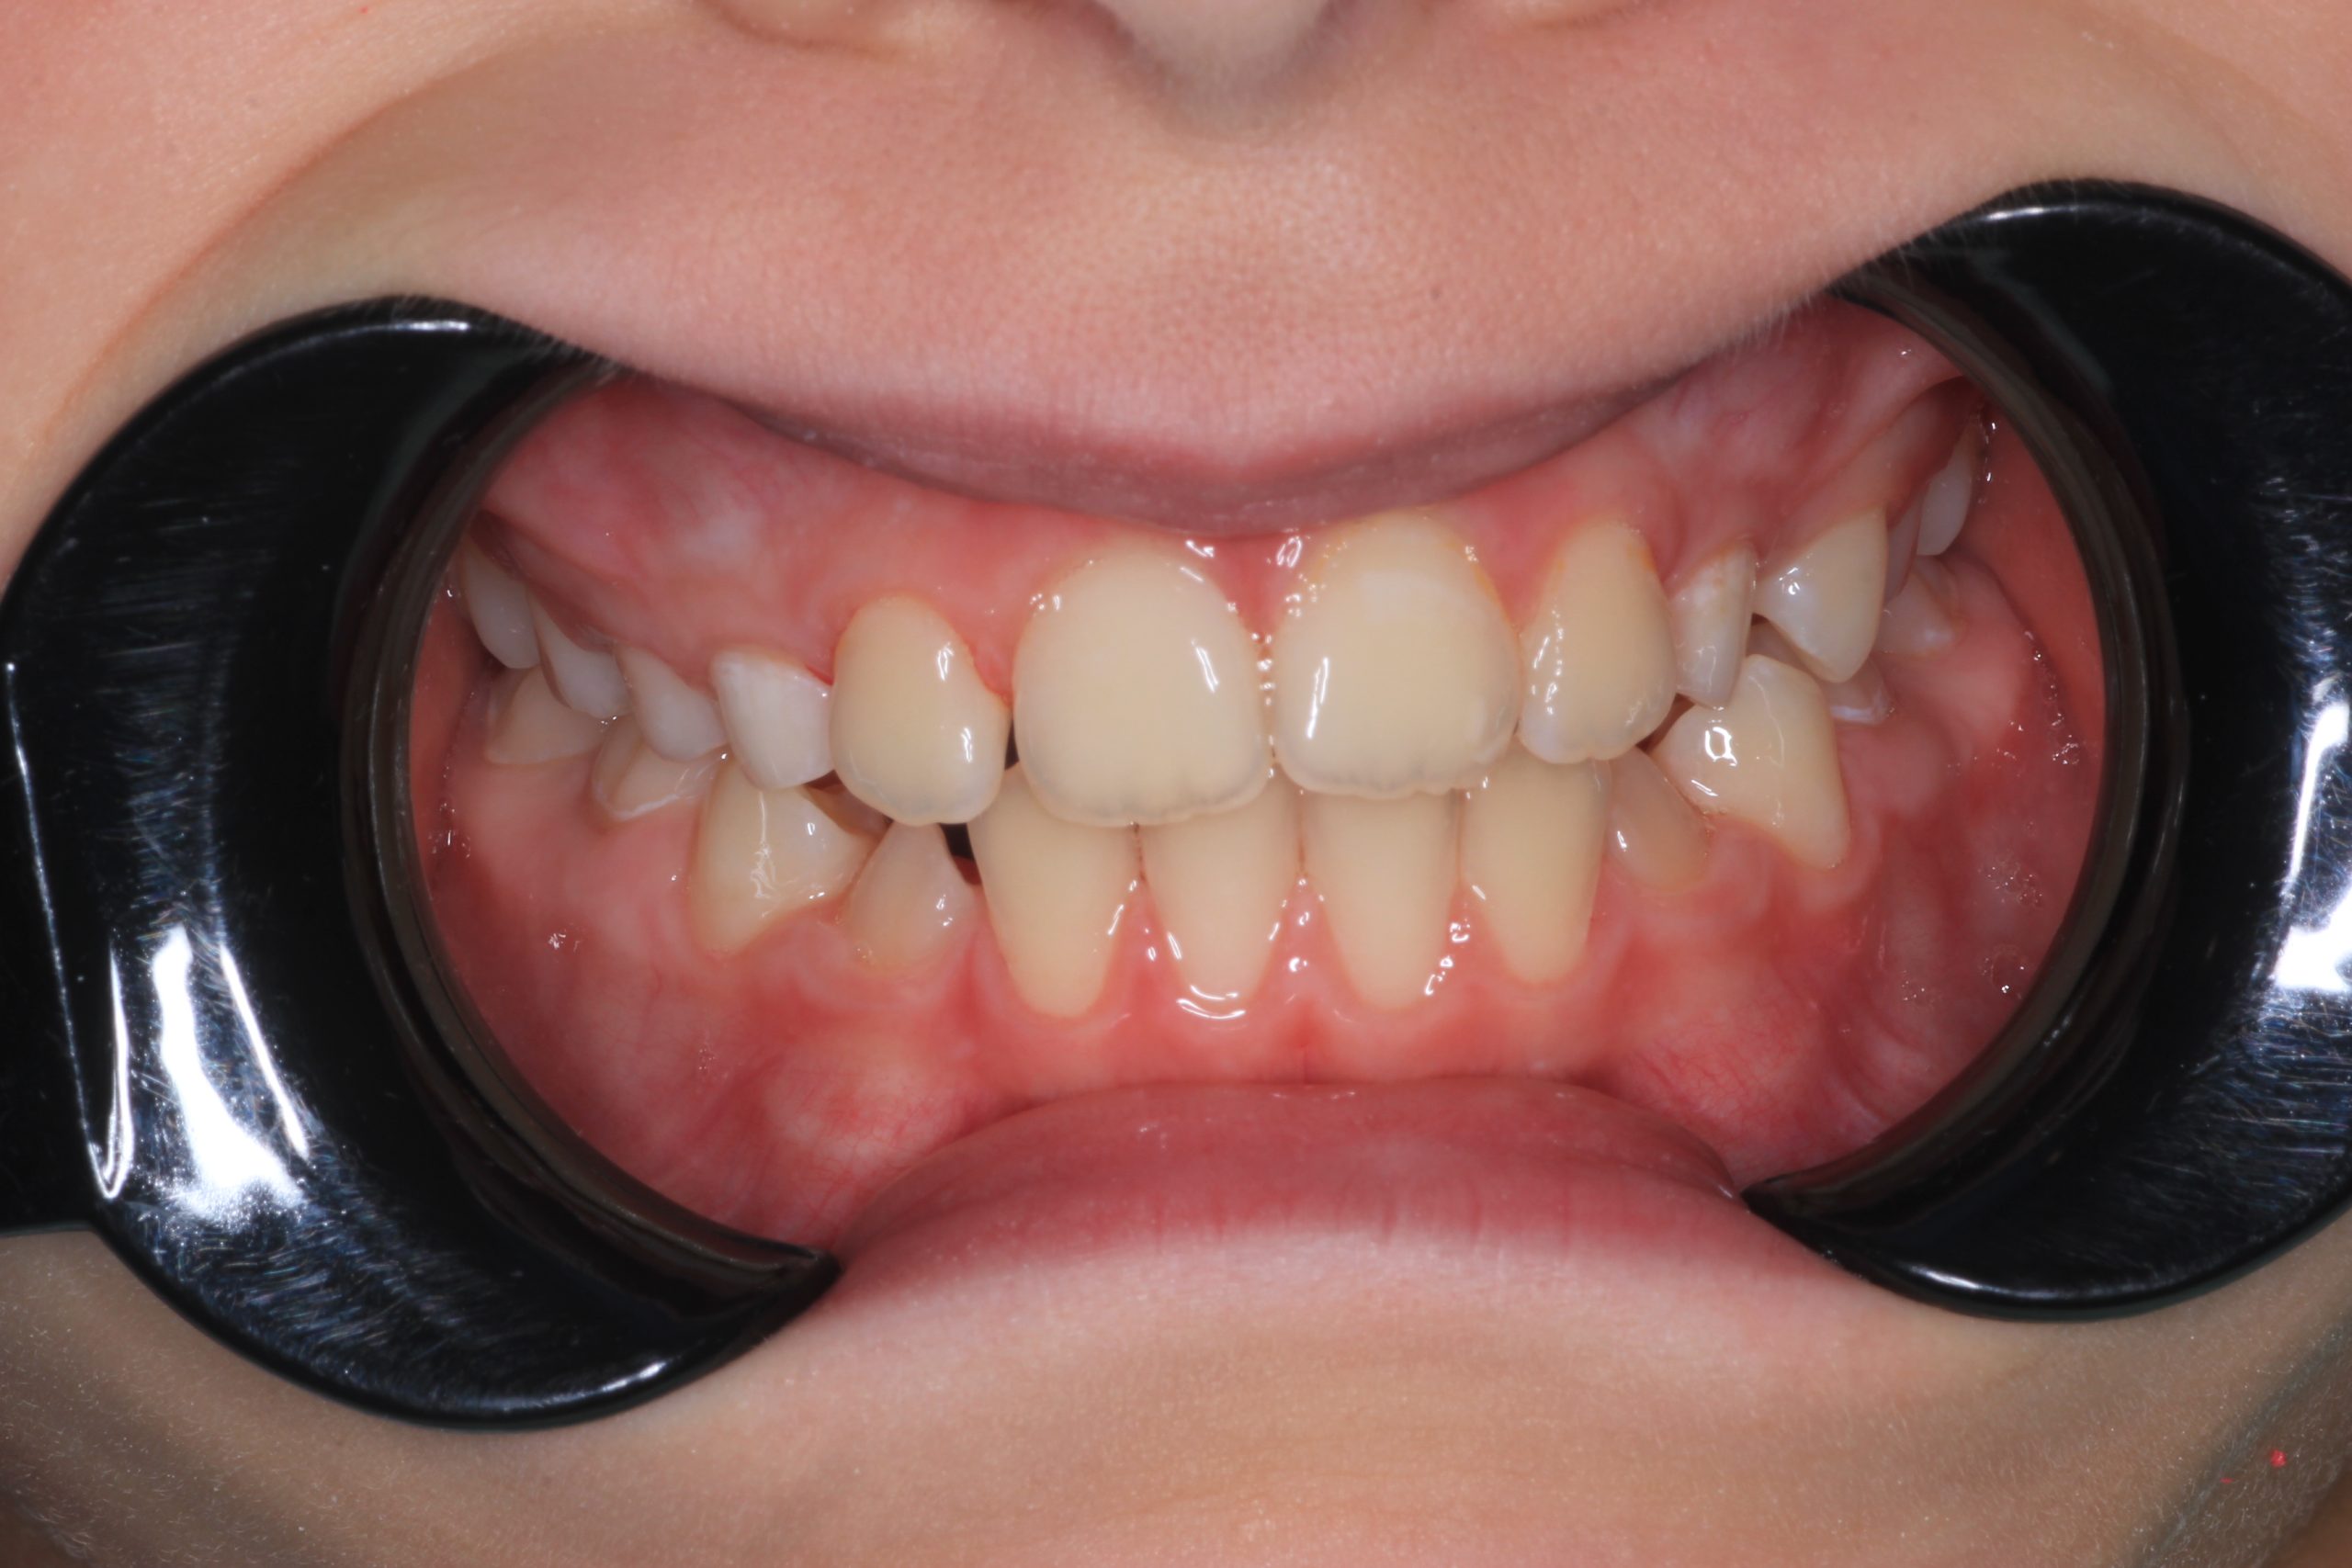

- Detailed Examination

We examine the condition of teeth, gums, and bite. - Plaque Disclosure with Special Indicators